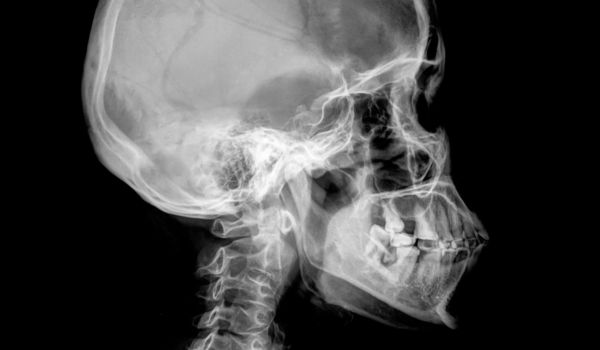

Рентгенодіагностика щелепно-лицевої ділянки. Що повинен знати рентген-лаборант?